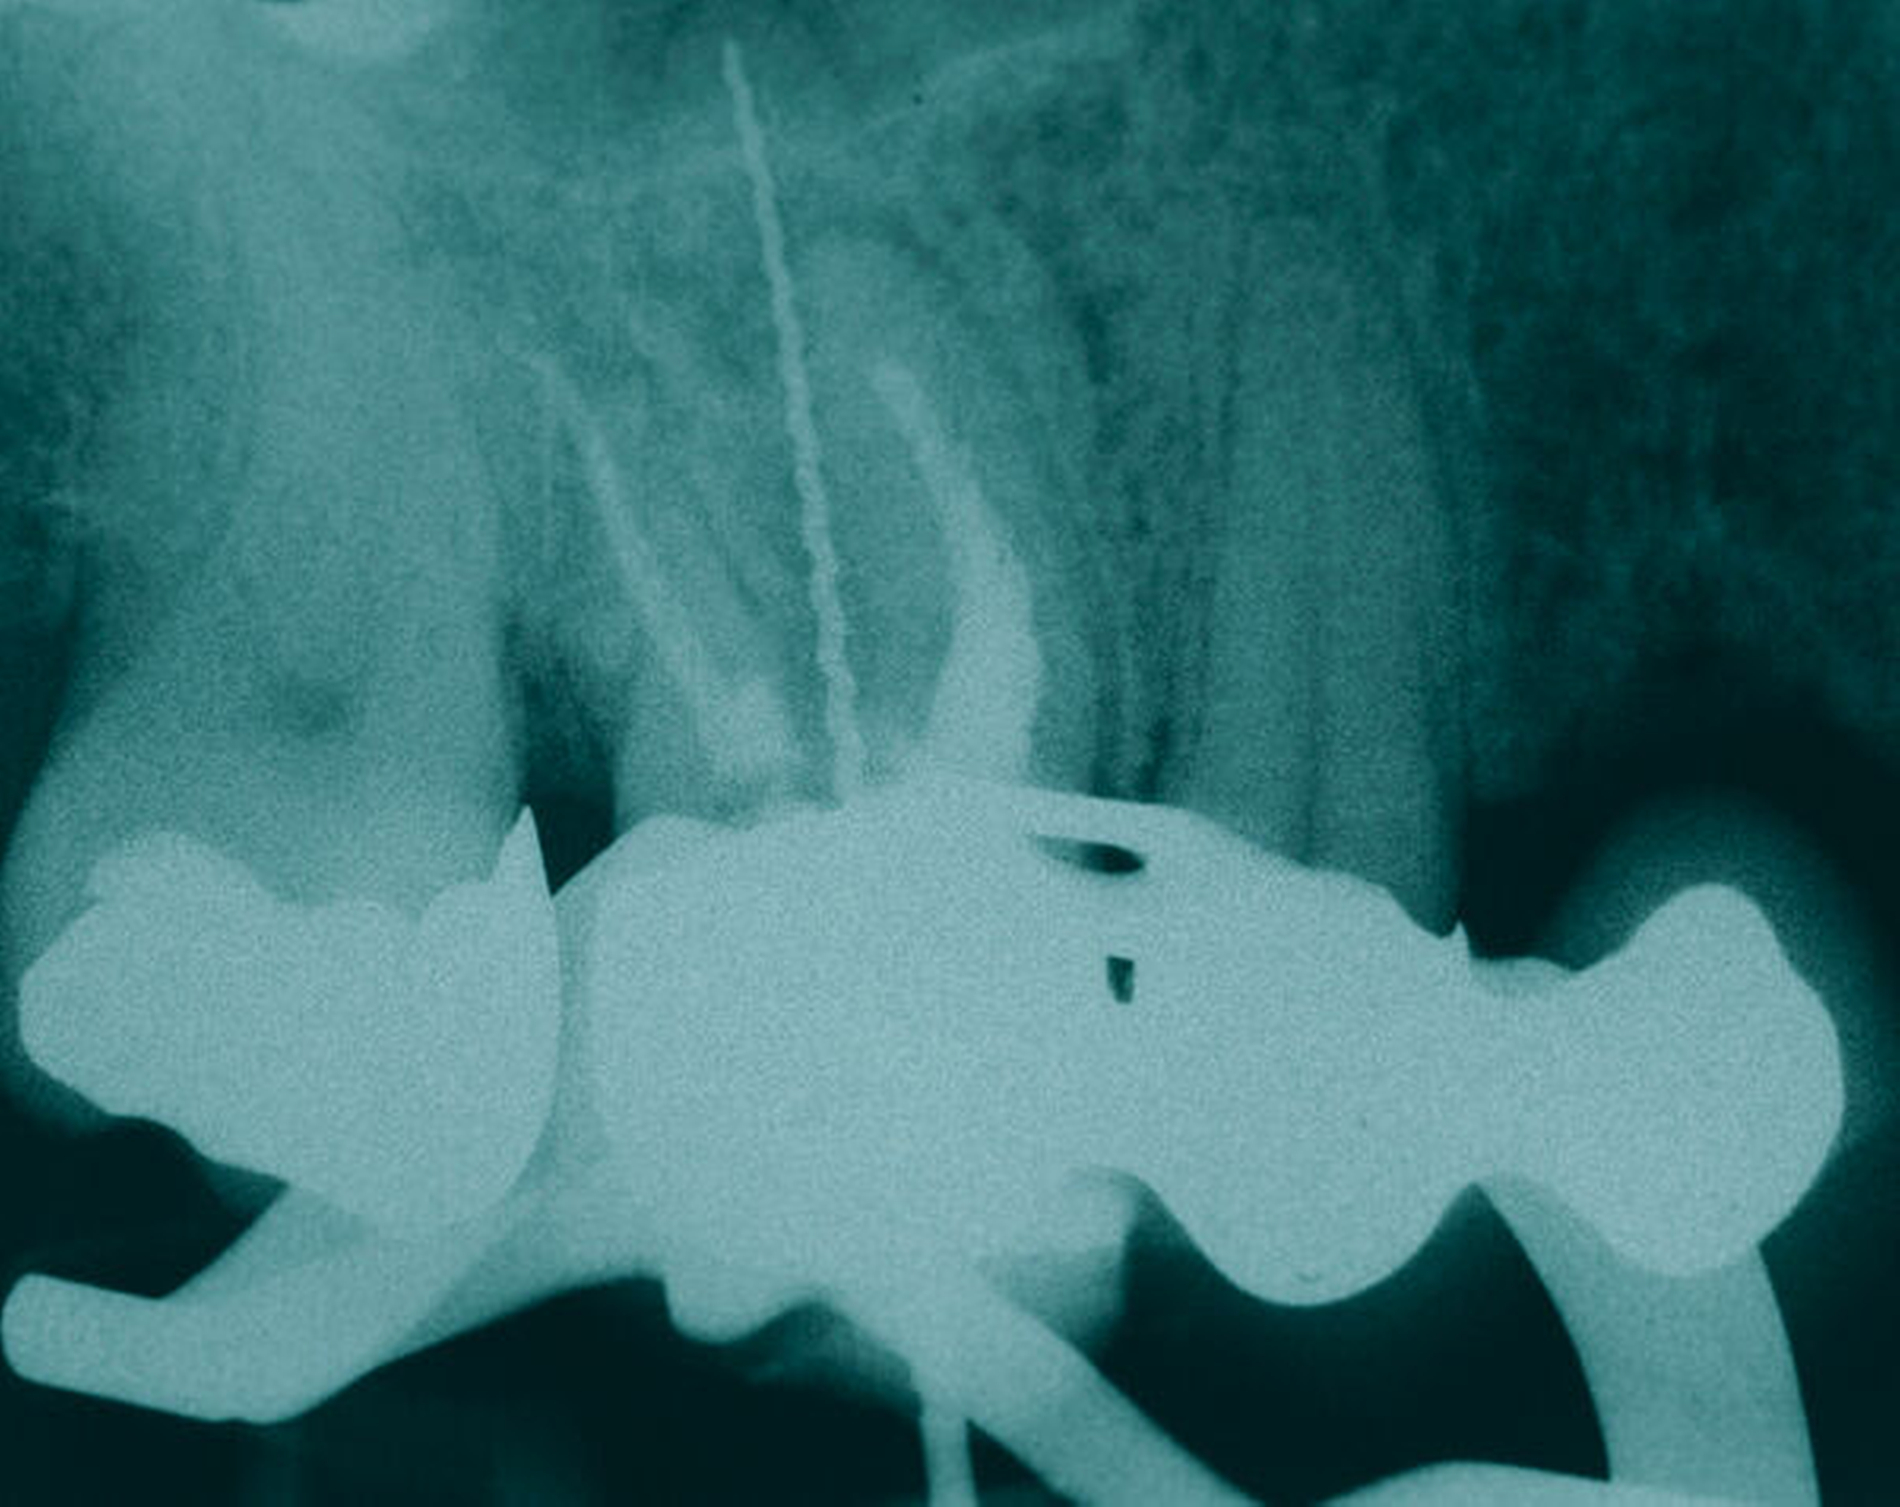

Eine 46-jährige Patientin klagte 2014 über wiederkehrende Beschwerden an Zahn 16, die sich auch nach einer endodontischen Behandlung nicht besserten. Wiederholt waren submuköse Abszesse aufgetreten. Lokalisiert war die Sondierungstiefe stark erhöht, was auf eine Längsfraktur der mesiobukkalen Wurzel hindeutete. Die Patientin wurde über die Möglichkeiten der Amputation der mesiobukkalen Wurzel sowie alternativ der Extraktion des Zahnes aufgeklärt und entschied sich für den Versuch des Zahnerhalts mittels Teilamputation der mesiobukkalen Wurzel.

Im Rahmen der Versorgung erfolgte auch ein Austausch der Extensionsbrücke 16–14 durch Einzelkronen auf 16 und 15 sowie einer Implantatversorgung mit Einzelkrone in Regio 014. Der Erhalt des Zahnes 16 ermöglichte so eine wenig invasive Versorgung des ersten Quadranten mit guter Hygienefähigkeit. Alternativ wäre bei Extraktion des Zahnes die Versorgung beispielsweise mit einer ausgedehnten Brückenkonstruktion von 13–17 oder einem weiteren Implantat in Regio 016, vermutlich mit (indirektem) Sinuslift, notwendig gewesen. So konnte der Fall minimalinvasiv zufriedenstellend gelöst werden. Die Patientin ist seit dem Eingriff beschwerdefrei und kommt gut zurecht. Die Situation ist nun seit sechs Jahren stabil.